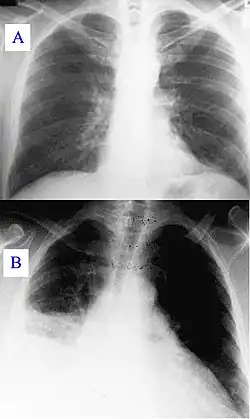

A) Normal chest radiograph; B) Q fever pneumonia affecting the right lower and middle lobes. Note the loss of the normal radiographic silhouette (contour) between the affected lung and its right heart border as well as between the affected lung and its right diaphragm border. This phenomenon is called the silhouette sign

In radiology, the silhouette sign refers to the loss of normal borders between thoracic structures.[1] It is usually caused by an intrathoracic radiopaque mass that touches the border of the heart or aorta.[2] In other words, it is difficult to make out the borders of a particular structure - normal or otherwise - because it is next to another dense structure, both of which will appear white on a standard X-ray.[3] It may occur, for example, in right middle lobe syndrome, where the right heart margin is obscured, and in right lower lobe pneumonia, where the border of the diaphragm on the right side is obscured, while the right heart margin remains distinct.[2] Silhouette sign is very useful in localizing lung lesions as all structures forming cardiac silhouette are in contact with a specific portion of the lung.